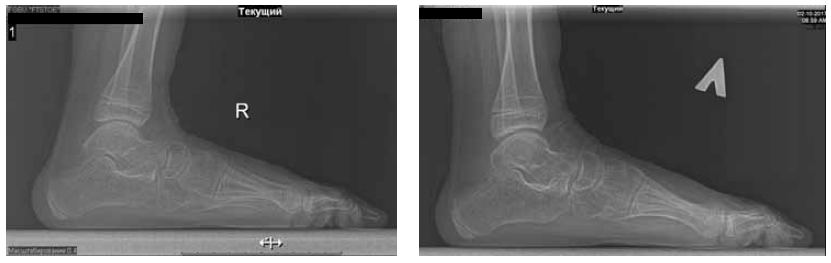

Patient Ch., 8 years old. Diagnosis: cerebral palsy with spastic diplegia and severe talipes equinoplanovalgus. The patient was admitted to the clinic with complaints of gait abnormality, deformity of the feet, and difficulty in wearing shoes (Fig. 2).

Fig. 2. Radiographs of the feet under load before the surgery: a — frontal view; b, c — lateral views